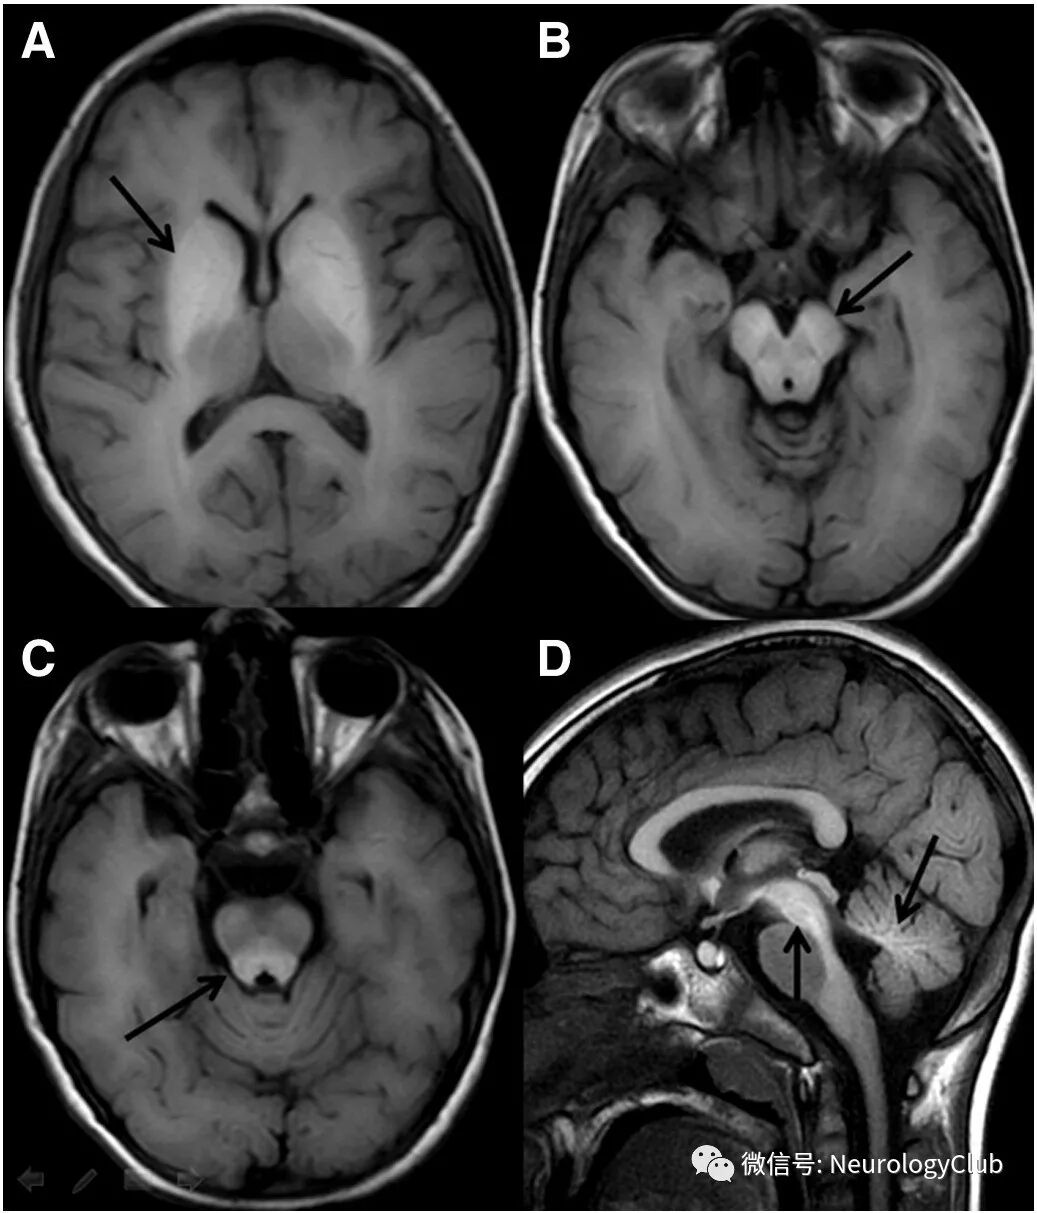

22岁女性,表现为进行性步态障碍和口齿不清4年。查体提示共济失调,眼球震颤,锥体束征,运动迟缓和足肌张力障碍伴鸡步(视频2)。未见踝背屈肌或跖屈肌无力。有共济失调家族史。MRI可见轻度脑桥小脑萎缩(图2)。基因检测证实为脊髓小脑性共济失调3型。

(图2:MRI可见轻度小脑和脑干萎缩[白箭])